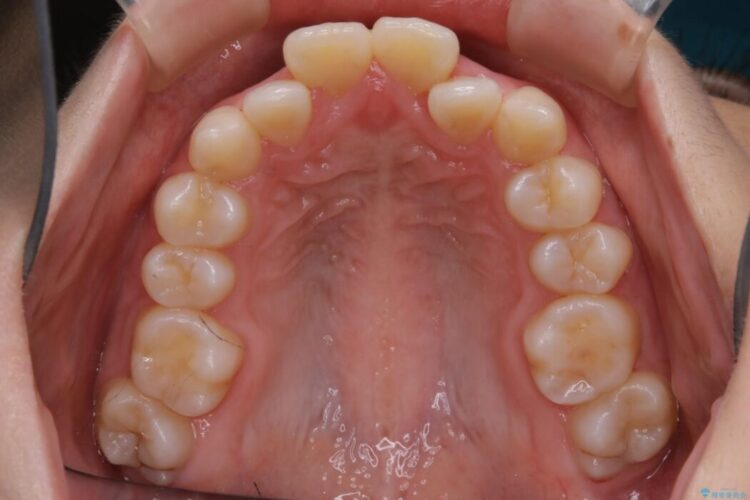

検査したところ歯に対して骨が上顎・下顎共に小さいことがわかりました。

それによりスペースが少なく歯列がガタついたり前方傾斜する生え方となっていました。

よって本症例では抜歯により歯の本数を減らすことにより整えるスペースを確保してワイヤー装置にて歯列矯正を行うこととしました。

本症例の患者様は顎の骨が小さく歯をきれいに並べるための隙間がないため、歯が重なったり傾斜してしまっていました。

抜歯を行うことによりスペースを確保し、小さい骨幅でも歯並びを整えることができます。